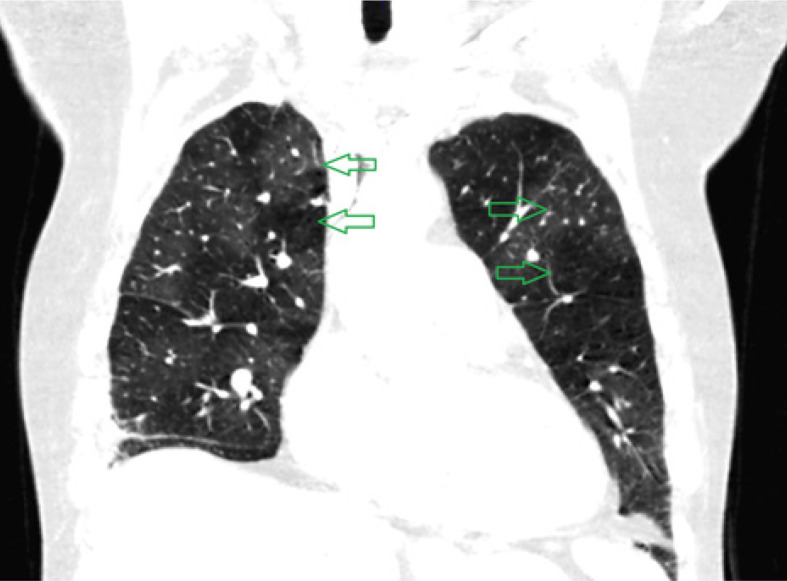

Results: CTEPH patients exhibited vessel narrowing, intimal irregularities, bands, and webs in all cases (100%), with the highest diagnostic value at the segmental level (AUC = 0.906). Mosaic perfusion and variability in vessel size demonstrated moderate predictive value (AUC = 0.740 and AUC = 0.788, respectively).